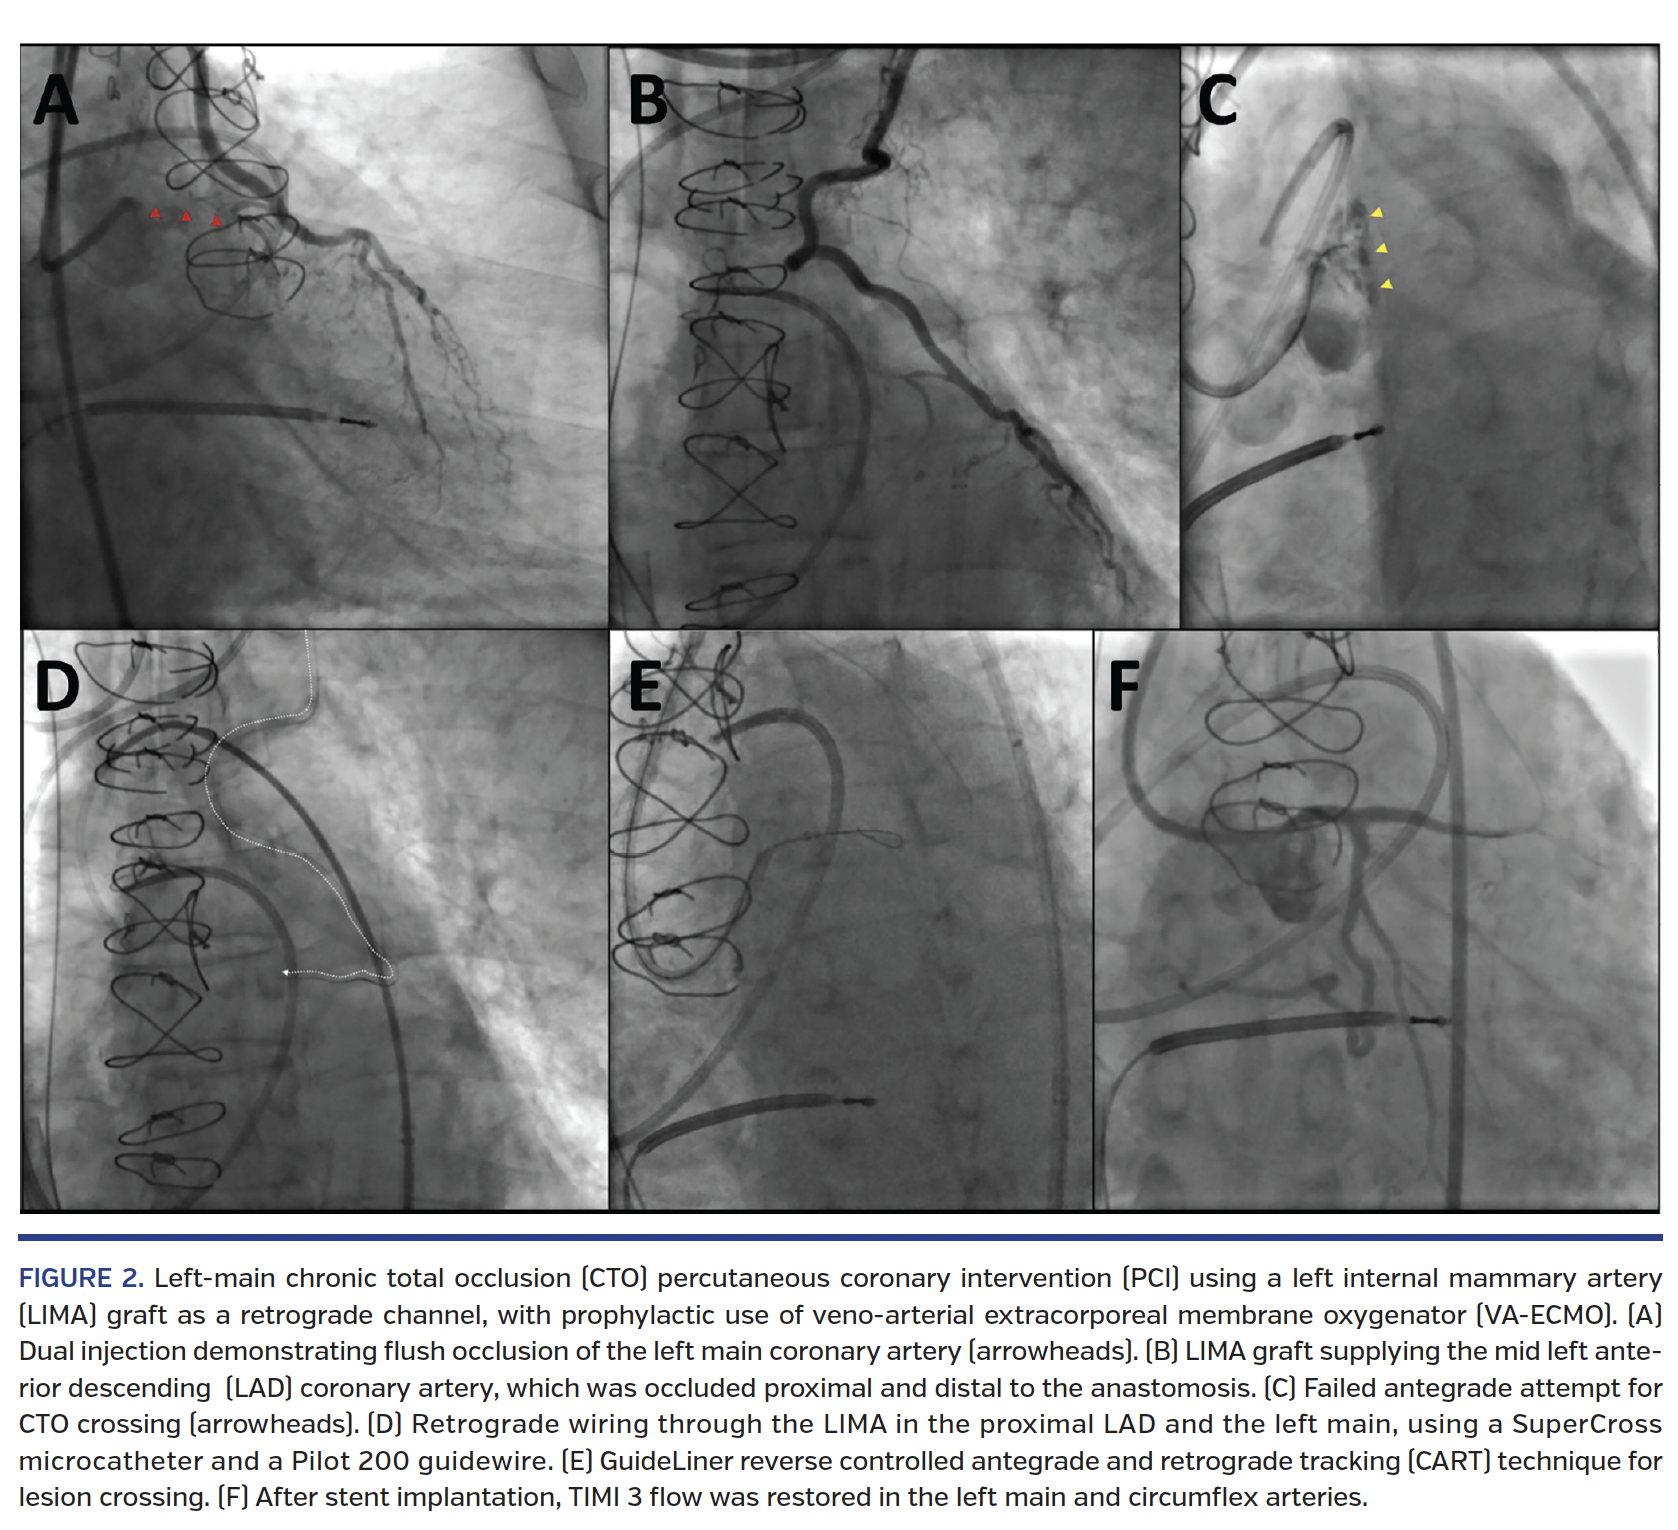

Overall, antegrade-wire escalation was attempted in 14 cases (70%), but was only successful in 1 case, after multiple failed retrograde or antegrade dissection re-entry crossing attempts. Antegrade dissection re-entry was used in 5 cases (25%) – in most cases after a failed retrograde crossing attempt – and was successful in 2 cases (10%) using Stingray-based re-entry (Boston Scientific) in 1 case and wire-based re-entry in the other. Retrograde crossing through a LIMA graft was attempted in every case and the CTO was successfully crossed in 12 patients (60%). In 11 cases, the lesion crossings were carried out via the LIMA graft, while 1 of them was crossed through a saphenous vein graft and an epicardial collateral. Among the successful retrograde cases, the following crossing techniques were applied: reverse controlled antegrade and retrograde tracking (CART) in 6 cases, GuideLiner reverse CART in 1 case (Figure 2), and true retrograde lumen puncture in 5 cases. Intravascular ultrasound tended to be used more commonly in the LIMA group (45.0% vs 31.4%; P=.20), as were guide-catheter extensions (40.0% vs 27.9%; P=.22).

Use of mechanical circulatory support was numerically higher in the LIMA vs non-LIMA group (23.5% vs 9.5%; P=.08). Mechanical circulatory support was used in 4 retrograde via LIMA cases (prophylactic in 3 and elective in 1); both Impella (Abiomed) and veno-arterial extracorporeal membrane oxygenator (VA-ECMO) were used. One patient initially had an Impella device that was changed to VA-ECMO due to progressive cardiogenic shock.